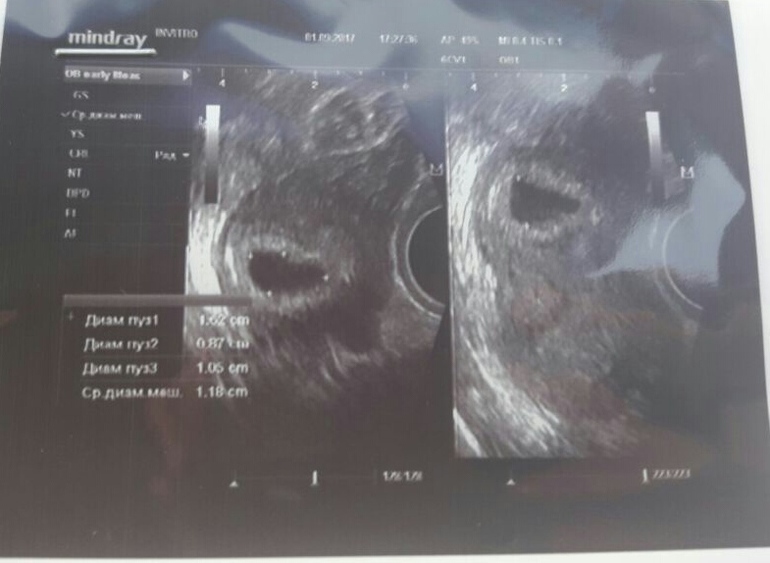

У меня по циклу 8-9 недель если не больше,месячные были 25 июня последний раз,по хгч 4-5,по узи 3-4,цикл такой же как у вас 60-65 дней,все хорошо,не переживайте,вы ж не знаете когда у вас овуляция была. У меня с дочкой месяц была разница между месячными и реальным сроком,поосто в вашем случае срок будет ставится по узи и хгч Кстати у меня хгч 14 661 сдавала в понедельник. На таком сроке еще нет сердцебиения, я пойду в 7 недель смотреть эмбрион и слушать сердечко и вообще сержечко слышно вроде только когда хгч за 20 000 перевалит вот мой хгч По узи плодное яйцо 7.1 мм

Хгч хороший, по УЗИ в 5 недель норм тоже, эмбриона ещё рано наверное увидеть!

по хгч через день-два должно быть 5 недель,по размеру яйца также 5 недель. почему вы думаете,что не развивается? я очень надеюсь в то,что все должно развиваться. тем более,что цикл нерегулярный.